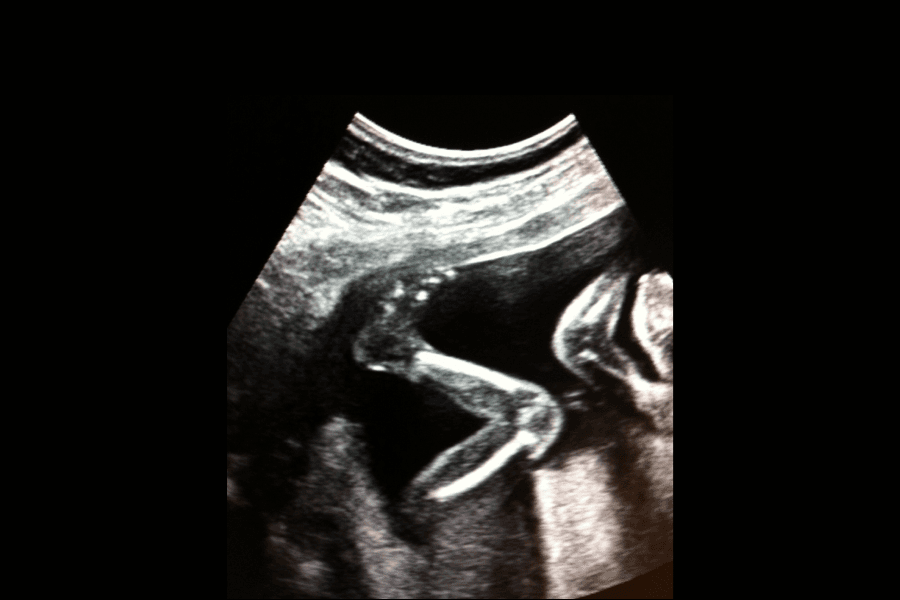

Towards the end of the pregnancy, you can often feel that the baby has periods of wakefulness, and not infrequently these correspond to how the baby will be awake or asleep after birth. During pregnancy, waking periods are characterized by a lot of movement and often these waking periods occur in the afternoon or evening. There is no evidence that the baby moves less at the end of the pregnancy, but the experience of the movements may feel different compared to before. Many people describe movements at the end of pregnancy as more sweeping or pressing, almost like twists.